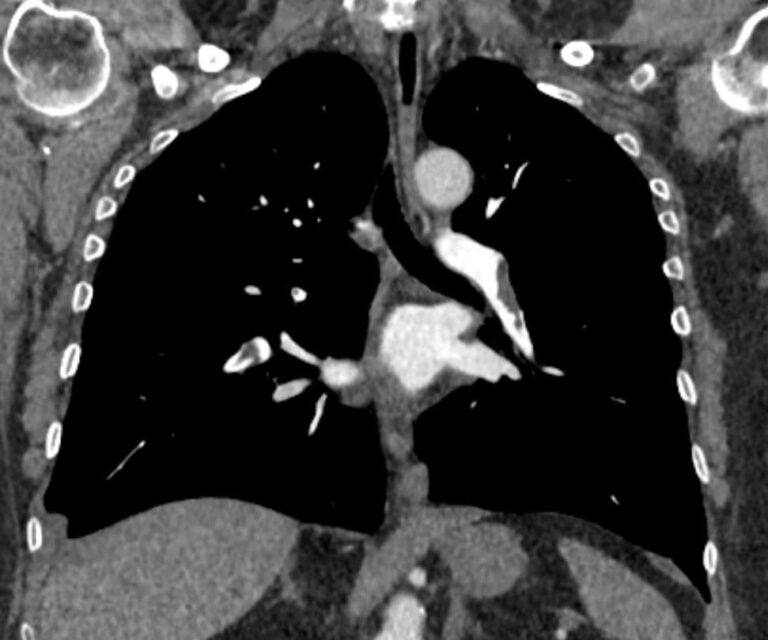

Тромбоэмболия легочной артерии характеризуется закупоркой просвета легочной артерии (либо самого легочного ствола, либо более мелких ветвей) тромбом. Тромб может образоваться в глубоких венах нижних конечностей, малого таза, часто после травм, операций, родов, а также в правом предсердии (на фоне нарушений сердечного ритма) и с током крови попадает в систему легочной артерии.

ТЭЛА может стать причиной внезапной смерти, а в некоторых случаях может приобретать хронический характер, когда тромбы малого размера закупоривают мелкие легочные артерии. В любом случае своевременная диагностика ТЭЛА может спасти жизнь больного.

Наиболее информативным, при этом быстрым и неинвазивным (то есть без вмешательства в организм пациента), методом диагностики патологии легочной артерии является мультиспиральная компьютерная томография (КТ-ангиография). Методика основана на использовании рентгеновского излучения в сочетании с цифровой обработкой данных для получения трехмерных изображений сосудистой системы.

Для визуализации кровеносных сосудов в обязательном порядке применяется контрастное усиление. Для этого в вену пациента вводится йодсодержащий контрастный препарат, который попадая в кровоток активно поглощает рентгеновские лучи и ярко контрастирует сосудистую систему, в том числе легочной артерии, на фоне окружающих тканей. Использование контраста дает возможность визуализировать даже мелкие артерии и выявить патологию.

• ТЭЛА (тромбоэмболия легочной артерии);